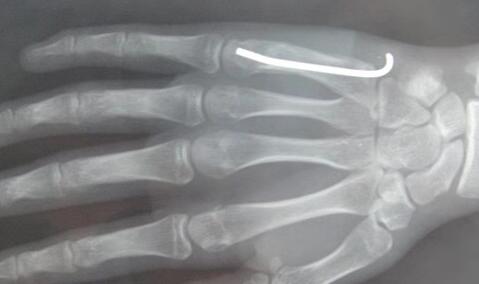

2.闭合手术,克氏针固定

复位一般比较满意,但是术后最好配合石膏固定一段时间